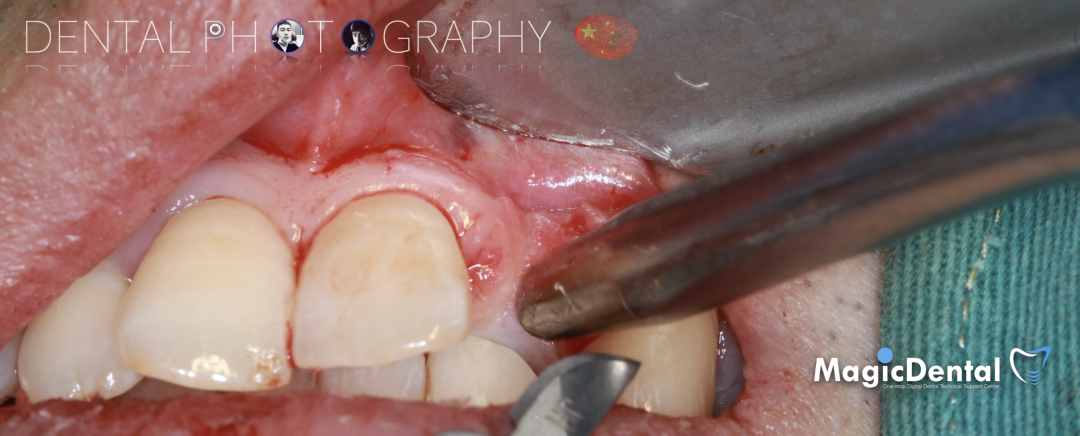

制作种植导板,局麻下切开,翻瓣彻底暴露术区,取出骨钉。

导板就位,种植窝洞预备,植入Nobel Active 3.5*15mm种植体一枚,植入扭矩35N,安装临时基台。